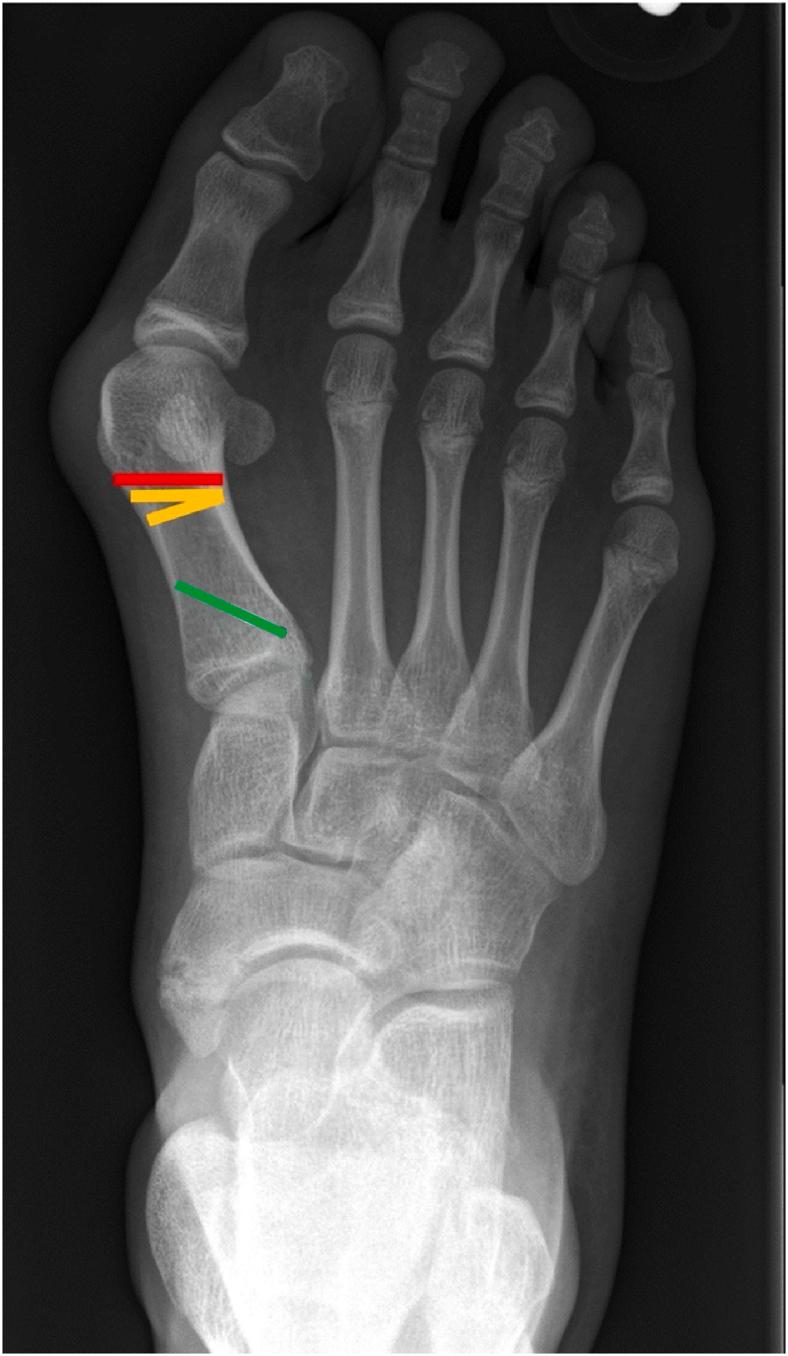

In adults, minimally invasive surgery for surgical treatment of hallux valgus has become increasingly popular, with a growing body of literature showing safety and effectiveness comparable to open surgery. Minimally invasive techniques for the treatment of juvenile hallux valgus include Bosch, Reverdin-Isham, Chevron, Endolog, distal soft tissue release, and hemiepiphysiodesis procedures. Data comparing minimally invasive and open surgery for the treatment of juvenile hallux valgus in children and adolescents are limited. In this review, we provide an overview of juvenile hallux valgus, discuss the minimally invasive techniques available for surgical treatment, and review the data on safety and effectiveness associated with each technique. There is a need for larger-scale studies comparing minimally invasive and open surgery for the treatment of juvenile hallux valgus, as well as the development of a standardized set of clinical and radiographic outcomes to guide evidence-based surgical management of juvenile hallux valgus.

(1)Compared with data on managing hallux valgus in adults, information on the safety and effectiveness of minimally invasive surgery for treating juvenile hallux valgus is limited.(2)Minimally invasive techniques for treating juvenile hallux valgus include Bosch, Reverdin-Isham, Chevron, Endolog, distal soft tissue release, and hemiepiphysiodesis procedures.(3)In total, 10 studies have assessed outcomes, demonstrating varying degrees of radiographic and clinical improvement along with complication rates.(4)Future large-scale comparative studies and standardized outcomes are essential for informing evidence-based surgical management of juvenile hallux valgus.